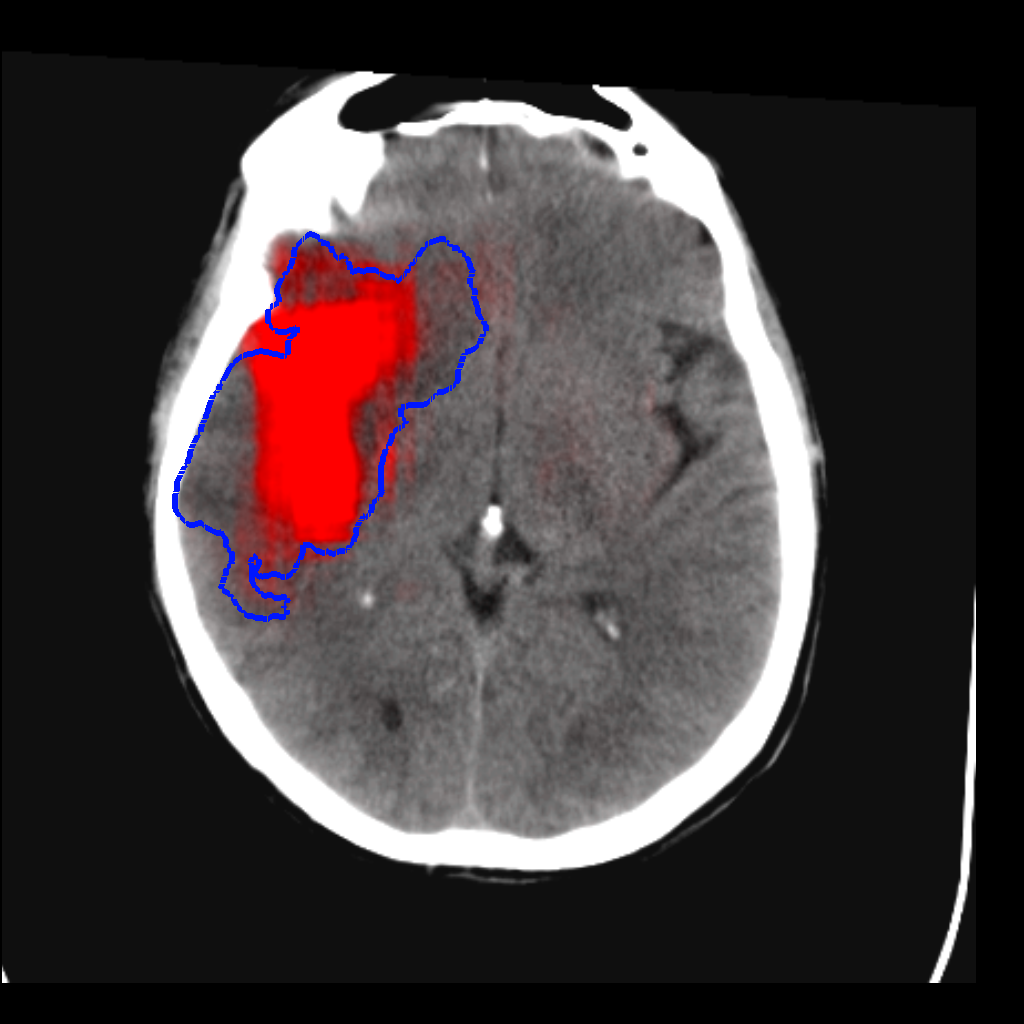

Fig. 3 shows a scatter plot and a Bland-Altman plot of the true and predicted volumes for all subjects in the testing folds using the proposed method. The mean volume error is -2.8 ml (the prediction is a slight underestimation) and the mean absolute volume error is 36.7 ml. The mean Dice score is 0.48. A representative set of predictions is shown in Fig. 4.